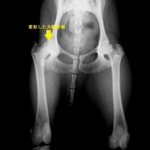

術前レントゲン

後肢の跛行を主訴に来院されました。レントゲン検査にて、左右股関節の形成不全および重度の関節炎所見を認めました。THRに関しては適応年齢(約9カ月齢以降)の範囲にありますが、左右とも長期に及ぶ骨関節炎の進行により、大腿骨頭・寛骨臼ともに重度の骨変形を伴っていました。このような症例において、THRのカップの定着が悪くTHRの手術の成功率が下がるため、機能回復の面では劣りますが、症状がより重いと判断された左後肢の大腿骨頭・骨頚切除術を実施しました。今後は、リハビリテーションを行い、患肢の機能回復に努めると共に、反対側の大腿骨頭・骨頚切除術を検討していく予定です。

股関節形成不全は成長期に発症する進行性の関節疾患です。若齢期でのTHRの選択が機能回復において最も優れています。好発犬種のワンちゃんは成長期からの定期的な股関節のレントゲン検査をお勧めいたします。(詳しくは上記の診断を参照してください。)